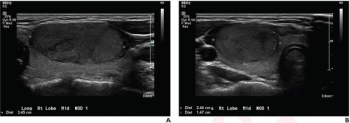

Emerging research showed the combination of contrast-enhanced ultrasound (CEUS) with perfluorobutane and modified 2017 LI-RADS criteria had comparable sensitivity, specificity, and accuracy to current magnetic resonance imaging (MRI) and computed tomography (CT) approaches to detecting hepatocellular carcinoma (HCC) lesions.